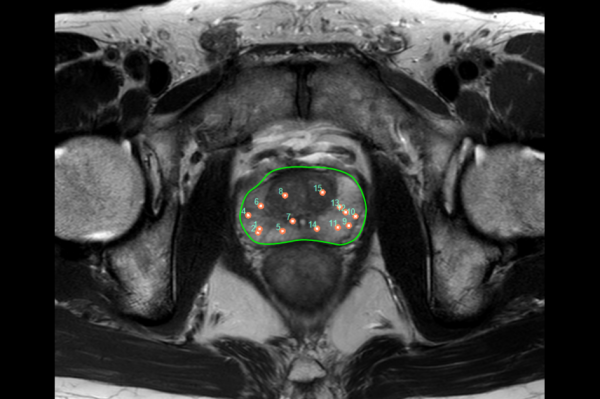

MRI は、前立腺の組織を視覚化するための最も正確な画像検査と考えられています。医師は MRI を使用して、生検が必要かどうかを確認したり、腫瘍の大きさや位置を調べたりします。

MRI は、前立腺がんの体積を推定し、前立腺がんを初期検出するのに最適な画像技術です。医師は前立腺がんを検出するために造影 MRI を使用することがよくあります。

マルチパラメトリック MRI は、前立腺がんを視覚化するのに最適なタイプのイメージングと考えられています。これは、前立腺のどこでがんが増殖しているかを特定し、医師にがんがどのくらいの速度で増殖するかを知るのに役立ちます。

医師はマルチパラメトリック MRI を使用して、がんが前立腺の外側に広がっているかどうかを確認することもできます。

マルチパラメトリック MRI は、複数の MRI 技術を組み合わせて前立腺の画像を作成します。標準的な MRI スキャンよりも詳細な画像が得られます。